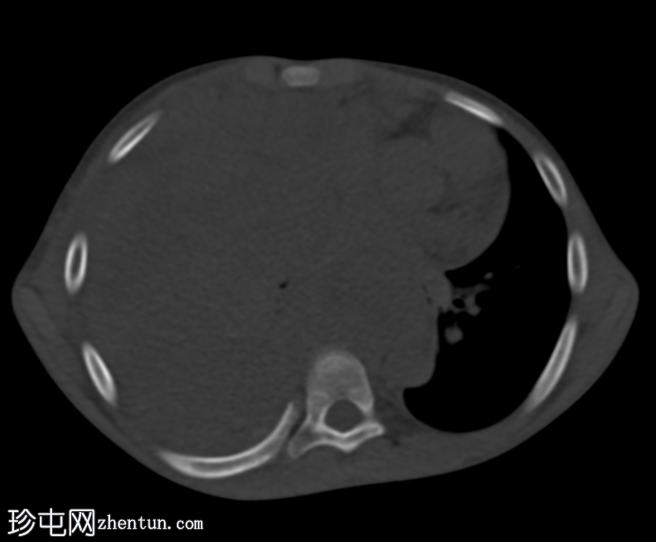

轴向

轴向非造影期

轴向骨窗

一个大的、不均匀强化的肿块占据整个右半胸腔,导致右肺几乎完全塌陷。肿块延伸至纵隔,导致观察到的纵隔移位。病灶内未见钙化。此外,右侧第三和第八肋骨后方可见轻微骨膜反应。

右侧第三和第八肋骨后方可见轻微骨膜反应,为反应性反应,不提示骨源性。肿瘤环绕右肺叶,提示其来源于胸膜。骨外尤文氏肉瘤也可起源于胸壁、肺或纵隔。它是一种恶性肿瘤,通常影响儿童和青少年。